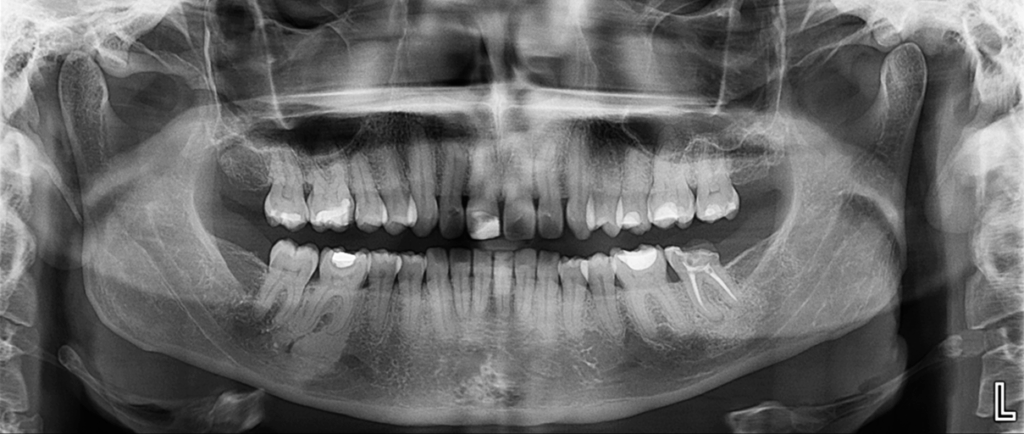

Radiografia Panorámica

En la radiografía panorámica se evidencian múltiples restauraciones coronarias. En relación con la pieza 37, se observa tratamiento endodóntico, proceso osteolítico periapical en la raíz mesial y un aumento de la densidad ósea circundante que se extiende hasta la cortical superior del conducto dentario inferior. Con respecto a la pieza 46, se observa una restauración coronaria extensa, un ensanchamiento del espacio para el ligamento periodontal periapical y un aumento de la densidad ósea periapical que se extiende hasta el conducto dentario inferior.